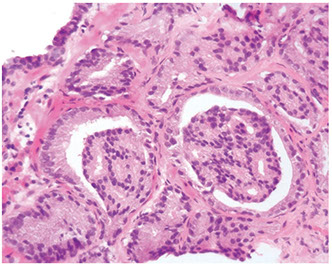

Intraductal Carcinoma of the Prostate (IDC-P)

Intraductal spread of a malignant prostatic AC

- frequently assoc c aggressive and high Gleason score invasive acinar adenocarcinoma

- is a prolif of pleomorphoic malignant cells (with nuclear sizes up to 6x nuclear sizes in adjacent invasive adenocarcinoma)

- expands ductal structures, but has at least a partial / patchy basal cell layer (rules out invasive acinar or ductal AC)

- rarely can be id'd on bx material in absence of infiltrating carcinoma

- vs HG-PIN, has a more dense cribriform pattern with overtly more solid than luminal areas (ie ratio of solid to luminal areas >70%)

- may show small cell-like change

- IDC-P on prostate bx is freq assoc c HG ca and poor px at radical prostatectomy

- thus most likely represents an advanced stage of tumor progression c intraductal spread of tumor in most cases

Infiltrating cribriform acinar AC (Gleason 4 or 5 c comedonecrosis) closely mimics cribriform IDC-P

- most cases if IDC-P would be dx'd as cribriform ca if IHC demonstrating basal cells had not been performed

- in some cases, contour and branching pattern of normal duct architecture suggests the dx of IDC-P as opposed to infiltrating ca

- the tx of IDC-P and infiltrating HG-prostate AC are the same, so distinction not critical on bx